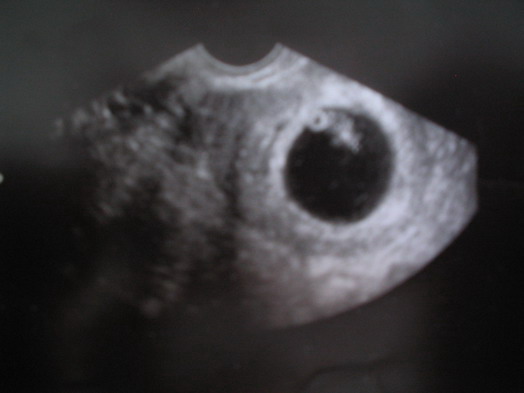

Dokihoz csak aznap jutottunk el, természetesen W.-hez mentünk és egy csomót izgultunk, hogy tényleg igaz-e, mert még mindíg nem mertük elhinni, de aztán megnyugtatott, hogy jó helyen van és tényleg ott van. Azon az UH- n még nem látszik csak egy pötty, úgyhogy nem is teszem fel, de a 21-i vizsgálatoon már szép petezsákot produkáltunk, benne Tökmag icipici teste is látszik a szikhólyaggal.

Kép